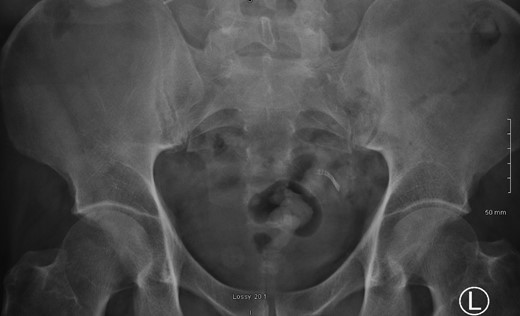

A 52-year male was referred to the surgical team for a 1-day history of left iliac fossa pain accompanied by nausea and the inability to open his bowels for 48 hours. The pain was 9/10 in severity, sharp, persistent and with a gradual worsening onset. The patient was previously diagnosed with extensive diverticular disease and admitted 2 months prior with acute sigmoid diverticulitis. 18 months earlier he underwent an emergent laparoscopy for an unclear pelvic inflammatory mass on CT, that suggested either severe sigmoid diverticulitis or appendicitis. He also had multiple polyps throughout the colon, that were endoscopically removed. The patients past medical history was significant for a non-flow limiting coronary artery disease, arterial hypertension and an allergy to penicillin and tetracycline. Temperature on admission was 38.7 C, blood pressure of 149/109 mm/Hg, pulse of 109 bpm and a respiratory rate of 20/min with O2-saturations of 96% on room air. The abdomen was soft with tenderness and guarding over the left iliac fossa. Bowel sounds were present. Investigations showed a white cell count of 17.6 tsd/ul and a CRP of 64 mg/l. No pneumoperitoneum was detected on an erect chest x-ray. Treatment with ciprofloxacin and metronidazole was started and the patient kept nil per mouth. CT imaging showed extensive sigmoid diverticular disease with marked pericolonic fat stranding and free gas tracking into the mesenteric fat. Gentamycin was added and within 3 days the patient’s clinical symptoms improved. He was apyrexic and the white cell count dropped to 10.9 tsd/ul. A repeat CT scan showed a stable appearing localized perforation with reduced free gas and no signs of collection. However, of note was a small curvilinear metallic foreign body within the lumen of the sigmoid colon of uncertain etiology (Fig. 1). On questioning, the patient recalled a mechanical fall with a head contusion 9 days prior to admission during which he lost his partial denture. The patient was commenced on laxatives and despite bowel movement on the following day, the foreign body did not pass. A PFA showed the persistent presence of the metallic foreign body over the sigmoid colon, which raised the suspicion of impaction (Fig. 2). The patient was prepared for colonoscopy and the foreign body was identified impacting the lumen of the sigmoid colon (Fig. 3). However, endoscopic retrieval failed and the decision was made to proceed with laparoscopic anterior resection. Intraoperative findings showed a rigid and thickened sigmoid colon with adhesions and a diverticular abscess. About 22 cm of sigmoid colon was resected and the procedure was completed with a primary colo-rectal end to end anastomosis, using a 31 mm CEEA-Stapler. The resected sigmoid colon contained the lost partial denture, which showed impaction and perforation into the sigmoid mesocolon (Fig. 4). Following surgery, the patient was transferred to the surgical ICU for 24 h observation and discharged home after one week.

PFA showed the persistent presence of a metallic foreign body over the sigmoid colon.